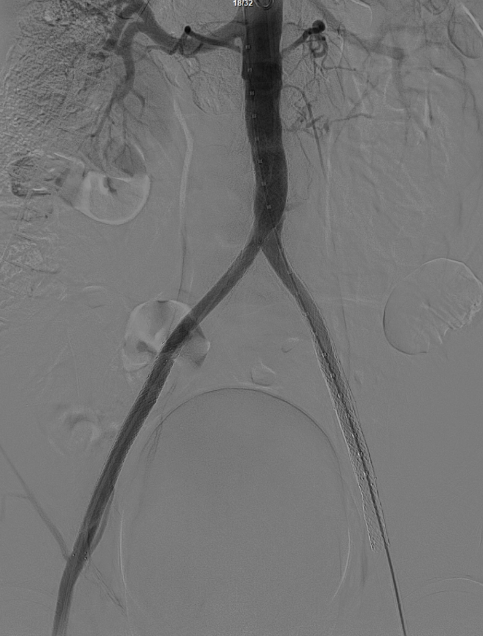

术前影像学评估:CTA显示腹主动脉下段闭塞,双侧髂总、髂外动脉支架内闭塞,右侧股动脉亦存在闭塞。结合急性加重病史,考虑为“基础狭窄+急性血栓形成”,不排除栓塞可能。

在超声引导下,成功完成双侧股总动脉穿刺。通过导管配合超滑导丝,顺利通过病变区域进入腹主动脉下段,造影明确腹主动脉下段及双侧髂动脉完全闭塞的病变范围与程度。

减容后造影显示仍存在重度残存狭窄,遂沿右侧股动脉置入VBX支架(直径11mm,长度59mm)。支架定位需满足近端完全覆盖腹主动脉病变段,远端距离双侧髂总动脉分叉至少1.5cm,以避免后扩张时大球囊对髂动脉造成损伤。

即时效果:造影显示腹主动脉、双侧髂总/髂外动脉及股动脉通畅。